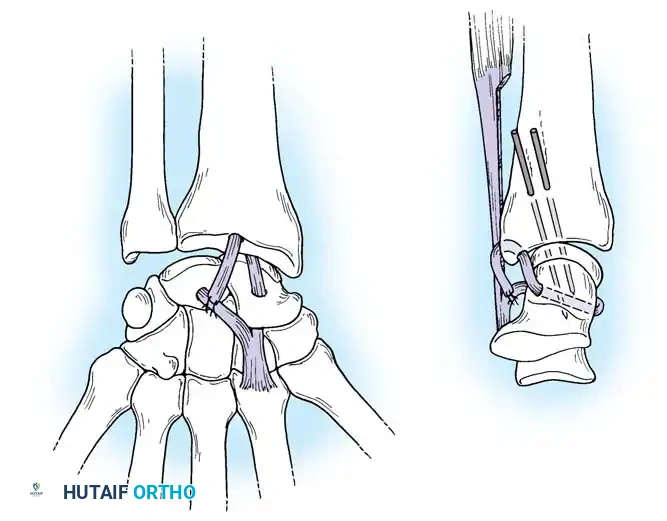

Closed reduction with percutaneous pinning (placing 0.045-inch K-wires from the scaphoid to the capitate and lunate) can be attempted. However, open reduction through a dorsal approach is generally preferred. This allows direct closure of the scapholunate gap, K-wire fixation, and primary repair of the dorsal SL interosseous ligament using suture anchors.